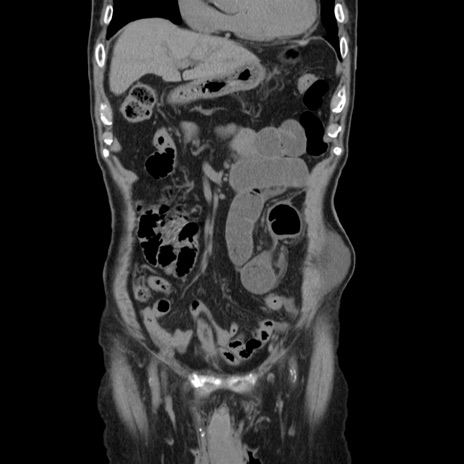

症例24(冠状断像)

【症例】80歳代男性

【主訴】左側腹部痛、嘔吐

【現病歴】本日早朝より左腹部に痛みあり。昼頃嘔吐認めたため、救急要請。

【既往歴】直腸癌(Mile手術)、胆摘

【身体所見】意識清明、BT 35.9℃、BP 221/93mmHg、SpO2 97%(RA) 、腹部:左ストーマ周囲に限局性の腹部膨隆あり。 膨隆部自発痛・圧痛あり・軟。

【データ】WBC 7700、CRP 0.09